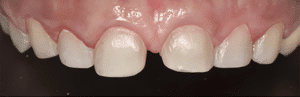

Les doléances de la patiente ont été traitées : elle ne présente plus aucune douleur et l’esthétique de son sourire a été restaurée (Fig.18).

Fig.18a à d : Vues finales.